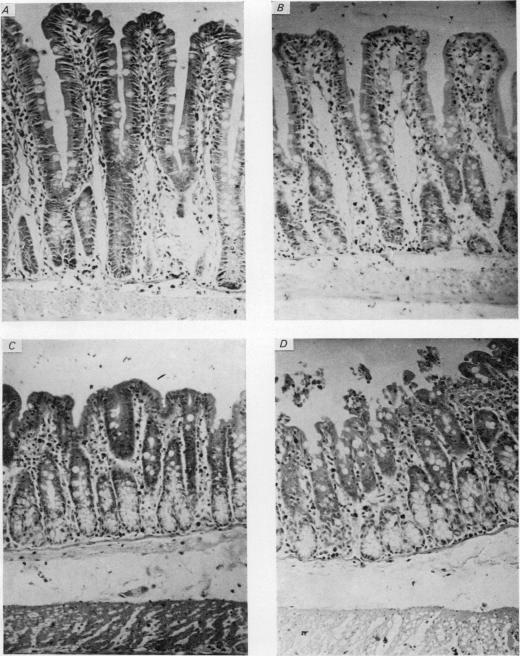

1. The location of the site involved in the secretory response of rat jejunum and colon to ACh was investigated by selectively damaging either the villi of the jejunum and the surface epithelium of the colon or the crypts. 2. The secretory response induced by ACh was measured both in terms of changes in electrical activity and chloride fluxes. 3. Exposure of the mucosa to 2 M-Na2SO4 for 30 min selectively damaged the jejunal villi and colonic surface epithelium but did not reduce the increased potential difference and current generated by ACh. 4. When resistance changes were taken into account the colonic response was markedly increased after Na2SO4 treatment although the jejunal response was unchanged. Under control conditions ACh reduced net Na absorption and stimulated Cl secretion by the colon. After exposure to Na2SO4 only the Cl secretory component of the ACh response remained, thus accounting for the enhanced effect. 5. Cycloheximide, administered I.V. at a dose of 12 mg/kg, damaged the crypts after 2 hr without affecting the villi of the jejunum or the surface epithelium of the colon. After cycloheximide treatment the increased potential difference, current and net Cl secretion induced by ACh were significantly reduced. 6. The crypts therefore appear to be the site primarily involved in the secretory response of rat jejunum and colon to ACh, although in the colon an inhibitory effect on the Na transport process located in the surface epithelium was observed.

1. 通过选择性损伤大鼠空肠绒毛和结肠表面上皮或隐窝,研究了大鼠空肠和结肠对乙酰胆碱分泌反应所涉及部位的位置。2. 根据电活动变化和氯离子通量来测量乙酰胆碱诱导的分泌反应。3. 将黏膜暴露于2M - Na2SO4 30分钟可选择性损伤空肠绒毛和结肠表面上皮,但不会降低乙酰胆碱产生的增加的电位差和电流。4. 考虑到电阻变化,尽管空肠反应未改变,但结肠反应在Na2SO4处理后明显增强。在对照条件下,乙酰胆碱减少结肠的净钠吸收并刺激氯分泌。暴露于Na2SO4后,乙酰胆碱反应中仅保留氯分泌成分,从而解释了增强的效应。5. 以12mg/kg的剂量静脉注射环己酰亚胺,2小时后损伤隐窝,而不影响空肠绒毛或结肠表面上皮。环己酰亚胺处理后,乙酰胆碱诱导的增加的电位差、电流和净氯分泌显著降低。6. 因此,隐窝似乎是大鼠空肠和结肠对乙酰胆碱分泌反应的主要涉及部位,尽管在结肠中观察到对位于表面上皮的钠转运过程有抑制作用。